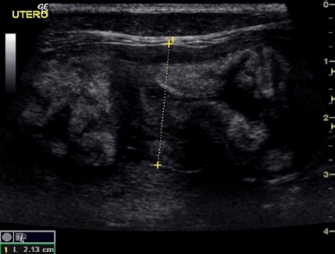

Eight intact female cats were referred for the treatment of FAC between 2015 and 2020. Ages at admission ranged from 8 to 12 months (Table 1). Four cats were domestic shorthair (C1, C2, C5, and C8), two cats were Maine Coon (C3 and C6), and two were Persian (C4 and C7). None of the cats received exogenous progestins but had a history of recent heats. Four cats (C5, C6, C7, and C8) had been mated and were between the 25th and 32nd day of pregnancy at presentation. The mammary glands were bilaterally enlarged, and no milk secretion was detected. Skin ulceration, inflamed, and painful mammary glands were present in six cases (C1, C2, C3, C5, C7, and C8) (Fig. 1a and b). General signs (tachycardia, lethargy, and anorexia) were strongly related to these changes. The diagnosis of FAC was based on clinical symptoms. Fine-needle aspiration biopsy of the mammary tissue was performed to support the clinical diagnosis. The combination of glandular-epithelial tissue and mesenchymal cells and the absence of prevalent immune cell populations in the cytologic smears allowed to exclude malignant growth or mastitis. Ultrasound examination of the mammary gland and doppler was employed to evaluate the structure and vascularization of the enlarged gland. FAC presented mainly as a well-circumscribed solid mass of granular, slightly hyperechoic texture, with regularly delimited margins. There was a uniform distribution of vascularity. Anechoic areas were present in the parenchyma and outside the margins (Fig. 2). Owners gave their consent to conservative treatment to preserve fertility and the integrity of the mammary glands. Mastectomy was not performed in any cases. Non-pregnant cats (C1, C2, C3, and C4) were treated on two consecutive days with subcutaneous injections of 15 mg/kg Aglepristone (ALIZIN; Virbac, Carros, France). The treatment was continued weekly with a single injection until the resolution of signs. If signs of ulcers, inflammation, or necrosis were evident in at least one mammary gland, 12.5 mg/kg q 12 hours of amoxicillin / clavulanic acid tablet formulation (SYNULOX; Zoetis, Rome, Italy) and 0.1 mg/kg q 24 hours of meloxicam (MELOXORAL oral suspension 0,5/ml; Dechra Veterinary Products, Turin, Italy) for the first day, followed to 0.05 mg/kg q 24 hours was given for 5–6 days. Furthermore, an oral dietary supplement containing maltodextrin and bromelain (BROSPET; Aurora biofarma, Milan, Italy) was administered once a day for the treatment period. Ulcers were treated topically twice daily with a cream containing hypericum and neem extract (HYPERMIX; Rimos, Mirandola, MO, Italy). The enlarged mammary glands were daily massaged with an emollient gel based on Aloe vera (ALOPET GEL; linea Angel Ariel, Grancona, VI, Italy). Two of the four pregnant female cats were treated with the same schedule for the severe enlargement and ulceration of the mammary glands (C5) and early signs of fetal resorption, deduced by the slow heart rate and the increased echodensity of amniotic fluid (C6). After 1 week, they presented bloody vaginal discharge, and ultrasound revealed four placental remnants in a cat (C6) (Fig. 3). Cloprostenol (ESTRUMATE; MSD Animal Health, Segrate, MI, Italy) at the dosage of 1.5 mcg/kg was given for three consecutive days to facilitate uterine emptying. Two pregnant female cats (C7 and C8) were treated with the schedule less the aglepristone drug to preserve the litters. In all the cases studied, after 2–3 weeks, the mammary gland reduced in size, and no ulcers or necrotic areas were detected, and after 4–5 weeks, the lesion was not more recognizable. At term, pregnant queens C7 and C8 delivered four and three kittens, which were normally nursed and weaned after 40 days (Fig. 1c). The case series is summarized in Table 1. A 1-year follow-up reveals no recrudescences of FAC in treated animals.

Fig. 2. Case C2. Ultrasound image of FAC revealed a solid pattern with a small cystic area and abundant oedema in the perimammary region.